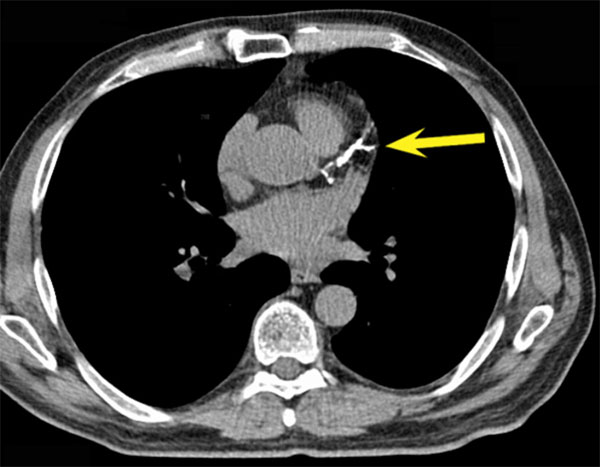

Компьютерная томография. Стрелка указывает на большую кальцинированную бляшку в коронарной артерии.